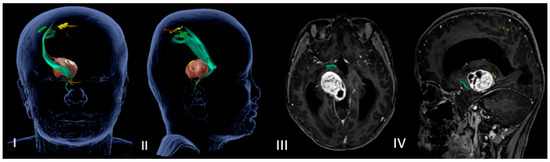

Finally, in all cases, we performed a postoperative brain MRI with gadolinium within 24 h of the surgery (Figure 3).

(a–d) Early postoperative brain MRI with gadolinium. (a,b) An early postoperative brain MRI, T1-weigthed with gadolinium in the axial (to the left) and coronal plane (to the right), for Case A in Figure 2. (c,d) An early post operative MRI, T1-weigthed with gadolinium, for Case B in Figure 1. In detail: In accordance with the nTMS data, we performed a transsylvian approach for Case A (a,b) obtaining a gross total resection (GTR). In Case B (b–d), we performed a trans-temporal approach, obtaining a subtotal resection (STR).